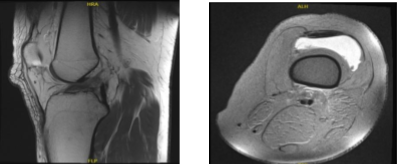

MRIs were reviewed and discussed with the patient and found significant results on his knee pain. Recent pivot shift injury resulting in a complete tear of the ACL and nondisplaced subchondral fractures at the lateral femoral condyle and lateral tibial plateau.

There are complex tears of both the medial and lateral menisci. A large displaced meniscal flap from the lateral meniscus extends into the meniscal tibial recess at the posterior horn/body junction. There is also mild cartilage loss in the lateral compartment and large joint effusion.

MRI-3T Left knee non-contrast